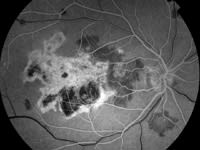

One year after initial presentation, patient presented with new blind spot in the right eye. Macular exam was significant for at least 3 new areas of inflammatory foci superonasal to the fovea and inferior to the optic disc (Figures 2A, 2B, 2C).

Figures 2A, 2B, 2C. 1 year after initial presentation, the macular exam was significant for at least 3 new areas of inflammatory foci superonasal to the fovea and inferior to the optic disc OD. | |